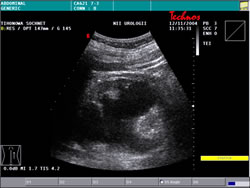

УЗИ: |

|